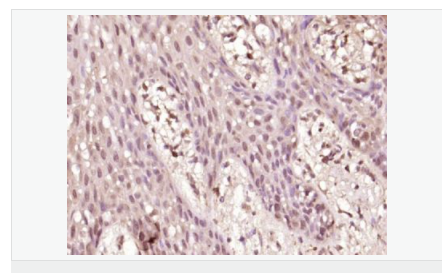

| 產品應用 | WB=1:500-2000 ELISA=1:5000-10000 IHC-P=1:100-500 IHC-F=1:100-500 Flow-Cyt=1μg /test IF=1:100-500 (石蠟切片需做抗原修復) not yet tested in other applications. optimal dilutions/concentrations should be determined by the end user. |